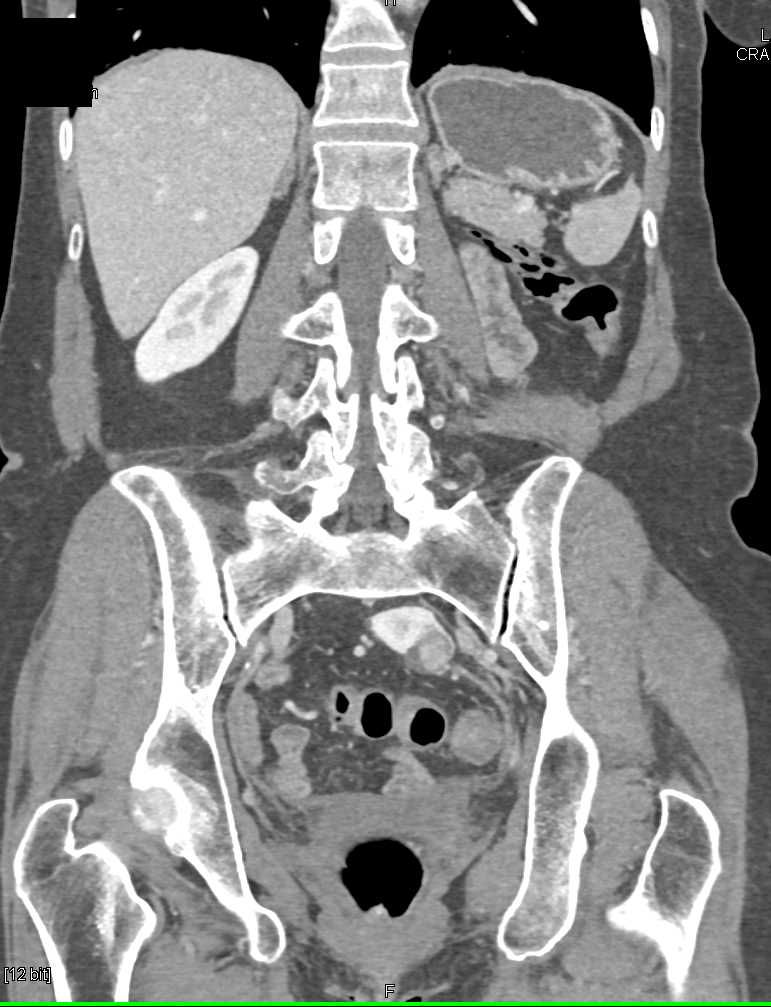

Renal Cell Carcinoma is a Solid Mass